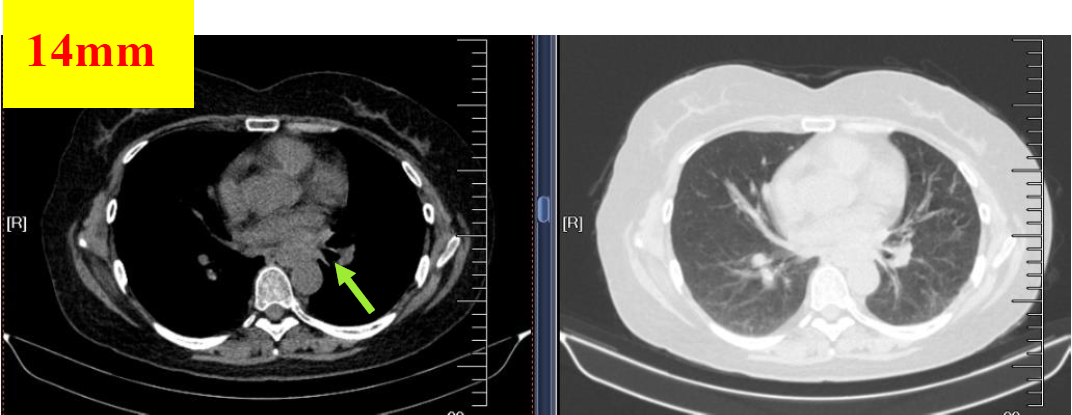

图5 2018.10.25影像学检查(PR)

图6 2018.12.04影像学检查(PR)